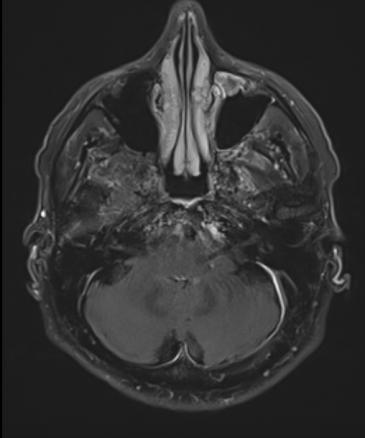

Pachyméningite sous-tentorielle

Épaississement de la méninge.